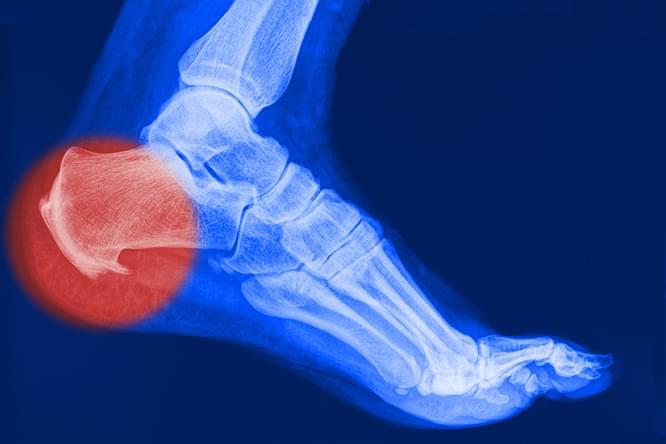

Все это явялется симптомами плантарного фасциита или более знакомого нам синдрома «пяточной шпоры». В большинстве случаев болевой синдром обусловлен воспалительно-дегенеративными изменениями плантарной (подошвенной) фасции.

Подошвенной фасцией называют жесткую сухожильную пластинку, которая прикрепляется к пяточной кости и головкам плюсневых костей, создавая своеобразный защитный чехол для подошвенной поверхности стопы. Она помогает поддержанию формы ступни и свода стопы. Нормальная анатомия стопы устроена так, чтобы человек при ходьбе не ощущал боли - для этого имеется подошвенный апоневроз, который играет роль амортизатора (мостика) для свода стопы. Подошвенная фасция натянута как тетива между костями и при каждом шаге эта своеобразная тетива натягивается, удерживая свод стопы, не давая костям стопы «разъехаться».

К сожалению, избыточный вес, повышенные физические нагрузки, высокие каблуки или тесная модельная обувь, плоскостопие приводят к тому, что подошвенная фасция в процессе ходьбы перерастягивает и травмируется, возникают микроповреждения волокон, воспаление.

Воспаление приводит к образованию отека, прорастанию микрососудов и мелких нервных веточек в поврежденную фасцию, возникает боль. Особенно сильно боль проявляется после ночного сна и покоя, так называемая «стартовая боль». Оставшиеся неповрежденными волокна подошвенной фасции начинают работать вместо разорванных, испытывая повышенную нагрузку, и тоже повреждаются. Воспаление и боль прогрессируют, заставляя снизить нагрузку.

Активность человека снижается, воспалительный процесс затухает и на месте поврежденных волокон возникают костные разрастания, которые видны на рентгенограмме и имеют характерный вид «шпоры»

Вот поэтому это заболевание и называют «пяточной шпорой», хотя сама «шпора» является уже результатом длительно протекающего плантарного фасциита.

Рентгенография пяточной области необходима для исключения перелома, если в анамнезе есть указания на травму. На ранних этапах формирования пяточная шпора на рентгенограмме не визуализируется.